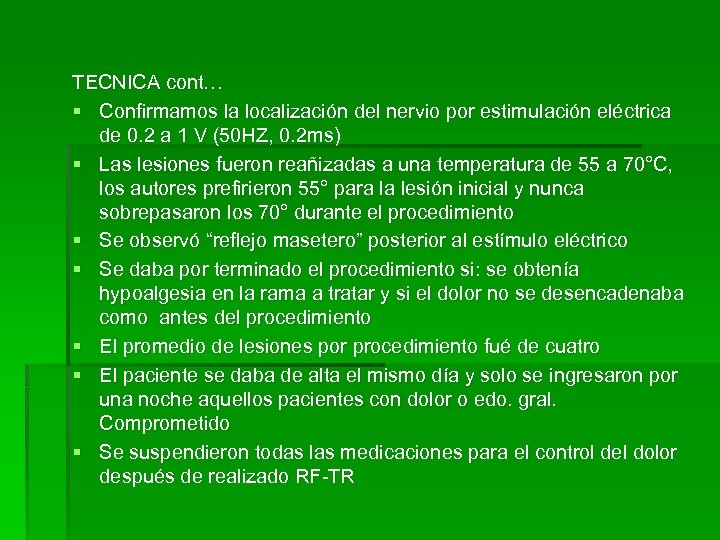

TECNICA cont… § Confirmamos la localización del nervio por estimulación eléctrica de 0. 2 a 1 V (50 HZ, 0. 2 ms) § Las lesiones fueron reañizadas a una temperatura de 55 a 70°C, los autores prefirieron 55° para la lesión inicial y nunca sobrepasaron los 70° durante el procedimiento § Se observó “reflejo masetero” posterior al estímulo eléctrico § Se daba por terminado el procedimiento si: se obtenía hypoalgesia en la rama a tratar y si el dolor no se desencadenaba como antes del procedimiento § El promedio de lesiones por procedimiento fué de cuatro § El paciente se daba de alta el mismo día y solo se ingresaron por una noche aquellos pacientes con dolor o edo. gral. Comprometido § Se suspendieron todas las medicaciones para el control del dolor después de realizado RF-TR

TECNICA cont… § Confirmamos la localización del nervio por estimulación eléctrica de 0. 2 a 1 V (50 HZ, 0. 2 ms) § Las lesiones fueron reañizadas a una temperatura de 55 a 70°C, los autores prefirieron 55° para la lesión inicial y nunca sobrepasaron los 70° durante el procedimiento § Se observó “reflejo masetero” posterior al estímulo eléctrico § Se daba por terminado el procedimiento si: se obtenía hypoalgesia en la rama a tratar y si el dolor no se desencadenaba como antes del procedimiento § El promedio de lesiones por procedimiento fué de cuatro § El paciente se daba de alta el mismo día y solo se ingresaron por una noche aquellos pacientes con dolor o edo. gral. Comprometido § Se suspendieron todas las medicaciones para el control del dolor después de realizado RF-TR